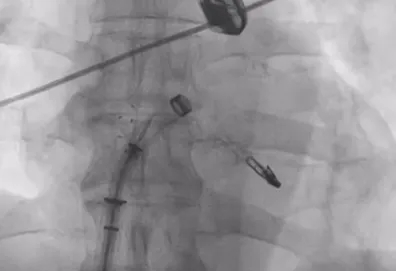

可降解房间隔缺损封堵器

选择靠下靠后穿刺位点,避开房间隔缺损封堵器,避免器械损伤

房间隔成功穿刺,穿刺位点距二尖瓣瓣环平面高度3.1cm,可使用高度不足